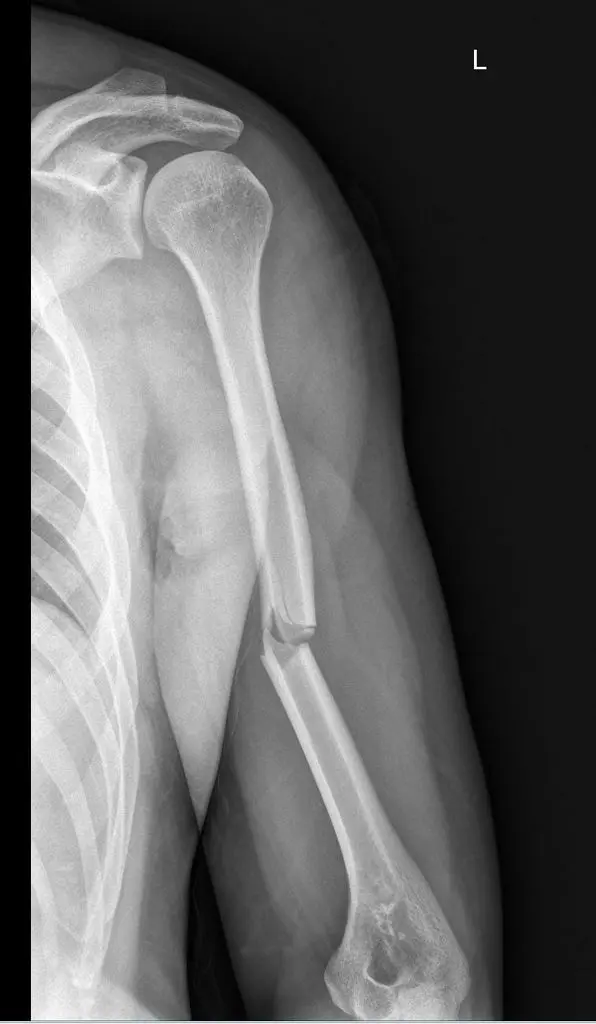

Mastering Humeral Shaft Fractures: Diagnosis & Treatment

- Humeral Shaft Throwing Fractures in Overhead Athletes: Advanced Epidemiology, Biomechanics, and Surgical Anatomy